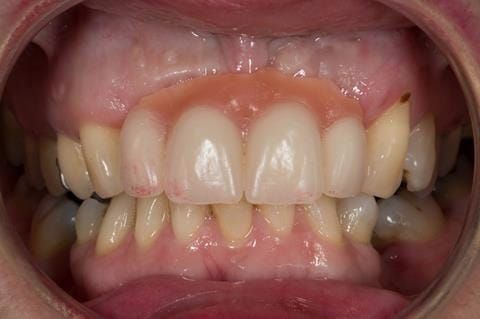

Provision of a maxillary cobalt chromium based partial denture/protective occlusal splint in a heavily restored dentition

- High smile line showing gum above gingival zeniths of upper front teeth when smiling. Aesthetic failure of the upper four incisors with inflammation of the gingivae and mis-match of the gingival zenith levels.

- Other than the maxillary incisors the remaining dentition was in marginally better condition being moderately to heavily restored. Many will probably require replacement and restoration from time to time mainly from wear and tear owing to occlusal forces.

Following consultation and second discussion appointment the patient chose to have option 3 namely, a maxillary cobalt chromium based partial denture/protective occlusal splint. The clinical situation and treatment process is shown in detail below with photographs. The patient was successfully rehabilitated with this and her quality of life considerably improved. The clinical work was provided by Finlay and the technical work by Rowan.